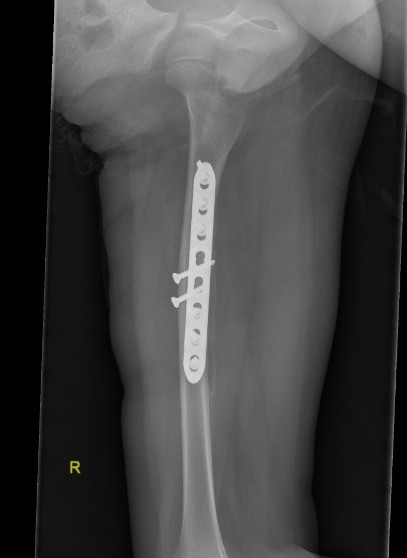

Femur plates

Indication

- length unstable fractures (spiral / comminuted)

- distal or proximal fractures

Options

Open plating

Submuscular bridge plating

Technique

- supine on radiolucent table or traction table

- proximal and distal incisions

- blunt dissection to periosteal layer

- run bristow or cobb elevator submuscularly

- 3.5 or 4.5mm LCP plate submuscularly

- indirect reduction techniques

- if inadequate reduction need to open